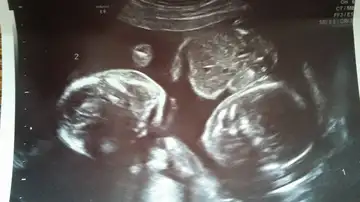

Unos gemelos, que compartían el mismo saco amniótico, salvan su vida por permanecer agarrados de la mano en el útero

Cada mujer vive su embarazo de una forma distinta. Hayley Lampshire y su marido Charlie han vivido "aterrorizados" su gestación desde que en la ecografía de la semana 12 descubrieron que esperaban gemelos y que ambos fetos compartían el mismo saco amniótico en lugar de tener cada uno el suyo.

Los médicos los alertaron de la gravedad de la situación, si los bebés se movían en el útero los cordones umbilicales podrían enredarse e incluso llegar a estrangularse entre sí. La única esperanza que tenían para que el final fuera feliz en esta historia es que los pequeños permanecieran quietos.

Hayley ha relatado a Mirror como recibieron la noticia. "Mi marido, Charlie y yo teníamos el corazón roto cuando nos enteramos de que nuestros bebés estaban en peligro". En una de las revisiones los padres comprobaron asombrados como sus pequeños estaban totalmente compenetrados pareciendo incluso que se daban la mano.

El embarazo fue avanzando y el pasado 25 de agosto ambos niños nacieron sanos y salvos con 36 segundos de diferencia. Ahora, Hayley quiere lanzar un mensaje de esperanza a todas esas parejas que viven una gestación de riesgo.